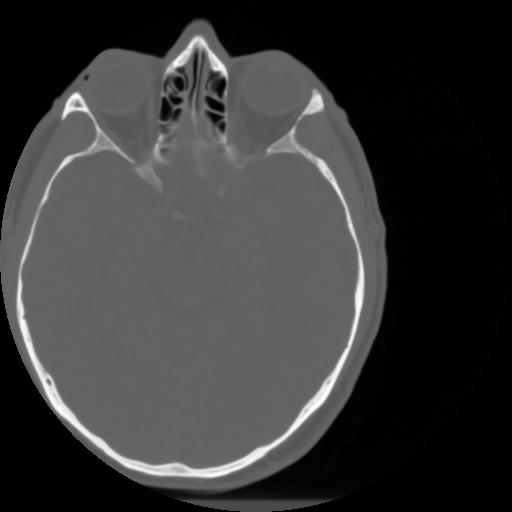

3 CEREBRO,,Axial,3.0,CEREBRO,,